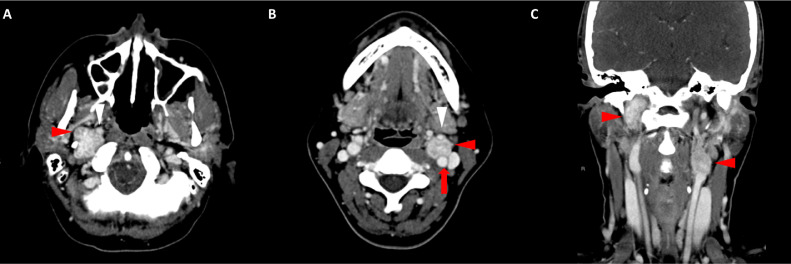

胸部、腹部和骨盆的對比增強動脈和靜脈期 CT 顯示多個圓形、主要是血管豐富的異質腫塊,具有囊性和實性成分,起源于胃底和胃體(圖 2-4)。 病變部分呈外生結構,被認為位于粘膜下層。 在頸部多發(fā)同步性副神經節(jié)瘤的情況下,賊初的鑒別診斷包括多發(fā)性副神經節(jié)瘤、多發(fā)性 GIST 以及轉移性疾病。

Fig. 2

圖 2:多發(fā)胃腸道間質瘤的軸位 CT 圖像。 (A 和 B)軸位動脈相增強 CT 圖像和(C 和 D)軸位靜脈相增強 CT 圖像顯示多個圓形、不均勻、增強的腫塊,具有實性和囊性成分。 腫塊位于粘膜下,結構呈外生。